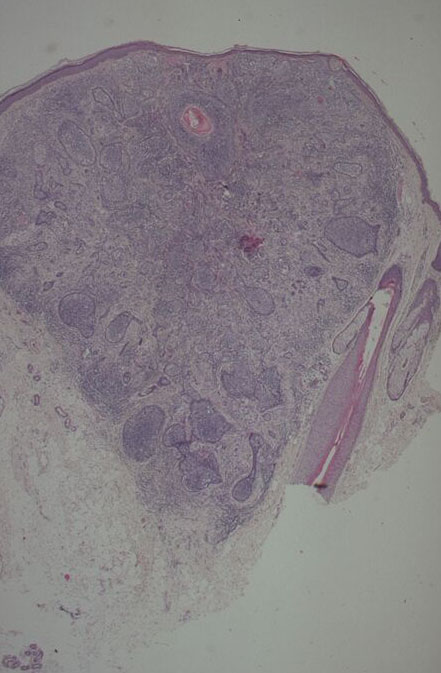

Cutaneous lymphadenoma =الغدوم اللمفاوي الجلدي